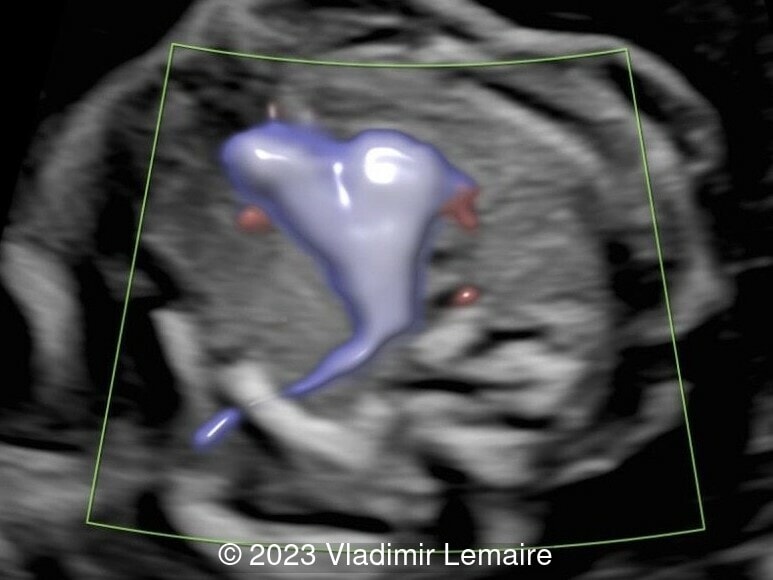

Aberrant right subclavian artery, seen in pink, in a fetus at 19 weeks of gestation.

Image 5 Aberrant right subclavian artery, seen in pink, in a fetus at 19 weeks of gestation.

Left subclavian artery, in the same fetus, coursing toward the left arm.

Image 6 Left subclavian artery, in the same fetus, coursing toward the left arm.